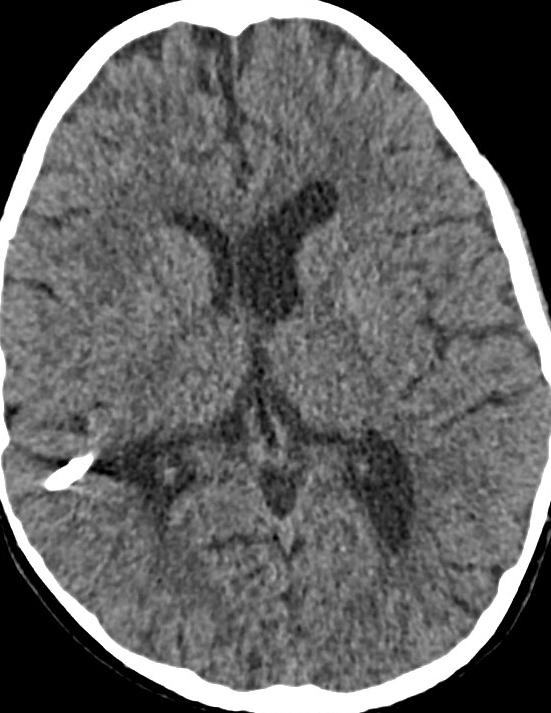

Here are a couple of slices of the CT from early Jan, showing mild enlargement of the ventricles compared to previous, but no evidence of transependymal CSF edema. The optic canals were felt to be slightly asymmetric, with the right being smaller than the left.